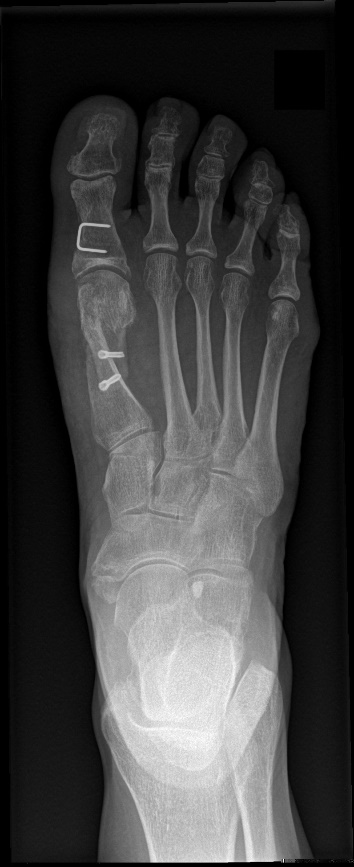

- Het verschuiven (osteotomie volgens SCARF) van het eerste beentje in de voorvoet (1e metatarsaal), daar dit beentje met de tijd progressief naar de binnenzijde van de voet verschoof. Deze osteotomie wordt dan gefixeerd met 2 speciale schroefjes welke tot aan de rand van het bot begraven zullen worden.

Voorbeeld van fixatieschroef: de TOOL-schroeven - Het is bijna steeds noodzakelijk om een wigje uit de basis van de grote teen te halen. Dit door een vaak voorkomende kromming t.h.v. de teen zelf en ook om de progressief ontstane torsie van de teen terug tot op de normale te brengen. Dit wordt nadien terug vastgezet met een krammetje. Afhankelijk van de type correctie wordt een schuin of recht krammetje geplaatst.

Schuin krammetje

Recht krammetje - Tenslotte wordt het binnenste kapsel dat te groot geworden was (zat gespannen over de bunion), terug mooi opgespannen door een speciale hechtingstechniek.